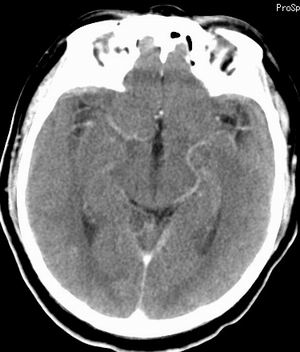

增强扫描:

平扫右侧岩骨与枕骨交角内侧脑质内见淡片状密度增高影,内缘清晰。增强图象上未见明显显示。

横窦乙状窦。

增强的横窦乙状窦。